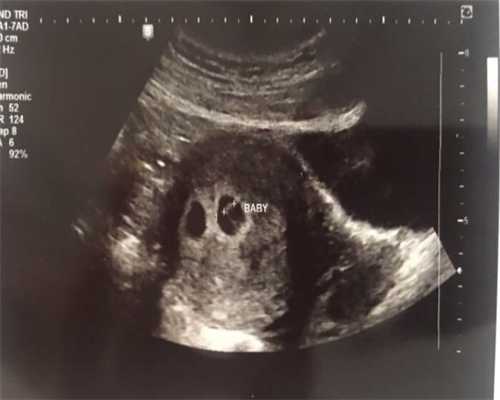

在第6-7周的时候,孕妇需要去医院做第一次产检,检查胚胎的发育情况,胎心胎芽是否正常。并在医院建立档案。此后,孕妇都应按时去医院做产检,及时了解胎儿生长发育情况。